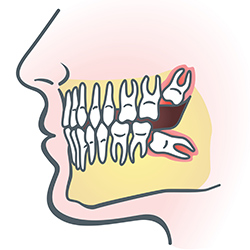

Wisdom Teeth

Wisdom teeth are types of molars found in the very back of your mouth. These teeth usually appear in late teens or early twenties but may become impacted (fail to erupt) due to lack of room in the jaw or angle of entry. When a wisdom tooth is impacted, it may need to be removed. If it is not removed, you may develop gum tenderness, swelling, or even severe pain. Impacted wisdom teeth that are partially or fully erupted tend to be quite difficult to clean and are susceptible to tooth decay, recurring infections, and even gum disease.

Wisdom teeth are typically removed in the late teens or early twenties because there is a greater chance that the teeth's roots have not fully formed and the bone surrounding the teeth is less dense. These two factors can make extraction easier, as well as making the recovery time much shorter.

In order to remove a wisdom tooth, your dentist first needs to numb the area around the tooth with a local anesthetic. Since the impacted tooth may still be under the gums and imbedded in your jaw bone, your dentist will need to remove a portion of the covering bone to extract the tooth. In order to minimize the amount of bone that is removed with the tooth, your dentist will often "section" your wisdom tooth so that each piece can be removed through a small opening in the bone. Once your wisdom teeth have been extracted, the healing process begins. Healing time varies depending on the degree of difficulty related to the extraction. Your dentist will share with you what to expect and provide instructions for a comfortable, efficient healing process.